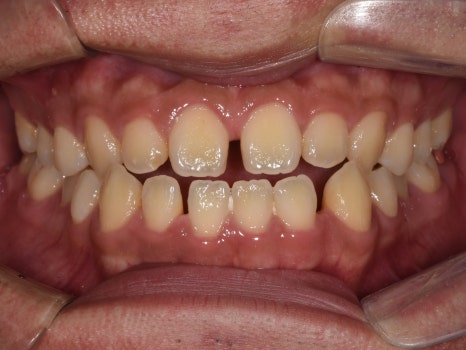

치료결과

실제 소요 기간 : 14개월

반대교합과 불규칙한 치아배열,

아래턱 돌출 등의 문제사항이

확연히 개선된 것을 알 수 있습니다.

아랫입술이 뒤로 들어가고,

반대교합이었던 앞니가

정상교합으로 자리잡은 것을

확인할 수 있습니다 :)